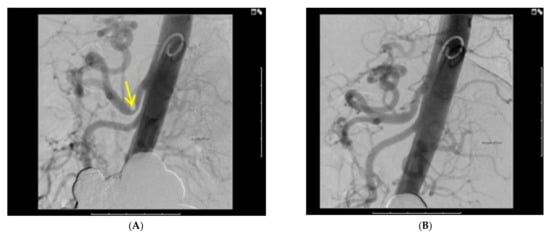

| Abdominal aortogram during expiration | 4 (100) |

| Narrowing of Celiac Artery on Abdominal Aortogram during expiration | 54% | 66% | 58% | 60% |

| Post-op Aortogram | normal | normal | normal | Not available |